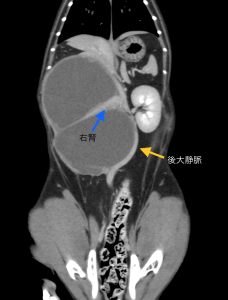

X線検査とエコー検査では、腫瘤が大きすぎて右区域の肝臓腫瘍か腎臓腫瘍か分からず…CT撮影と手術について説明させて頂き、翌日手術を行いました。

手術では、右の腎臓が10㎝以上の大きさに腫れており、中に赤黒いゼリー状の物質が詰まっていました。腫瘤は、後大静脈や左結腸動脈などの血管とべったり張り付いており、慎重に剥がして無事に摘出できました。

一般的に腎周囲偽嚢胞は、いろんな原因で腎臓の周りに水のような物質が溜まる病気のはず…この猫ちゃんは、腎臓の周りに硬いゼリー状の物質が溜まってしまったため、腎臓が押し潰されて、ペチャンコになってしまっていました。